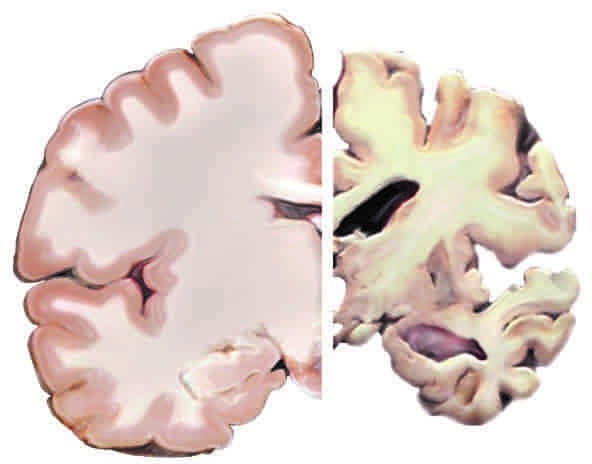

Οι επιστήμονες αναγνώρισαν τους υποδοχείς αναλύοντας τον εγκεφαλικό ιστό από 60 νεκρούς που είχαν μετάσχει στη μελέτη Religious Orders, η οποία παρακολούθησε 1.100 ιερείς, μοναχές και άλλα μέλη κληρικών για έως και 22 χρόνια για την κατανόηση του τρόπου με τον οποίο η γήρανση επηρεάζει τη γνωστική λειτουργία. Εκτός από τη διαπίστωση ότι οι υποδοχείς ινσουλίνης στον εγκέφαλο βρέθηκαν κυρίως σε μικροαγγεία – και όχι απευθείας στους νευρώνες, όπως πιστεύαμε προηγουμένως – οι ερευνητές παρατήρησαν επίσης ότι υπήρχαν λιγότεροι υποδοχείς ινσουλίνης τύπου άλφα-βήτα στους εγκεφάλους των ατόμων που είχαν διαγνωστεί με Αλτζχάιμερ. Όσο λιγότεροι είναι αυτοί οι υποδοχείς, τόσο περισσότερες αμυλοειδείς πλάκες της Αλτζχάιμερ συσσωρεύονται στον εγκέφαλό τους, με αποτέλεσμα τα άτομα, στη διάρκεια της ζωής τους να παρουσιάζουν χειρότερα αποτελέσματα στα τεστ για τις γνωστικές του λειτουργίες.